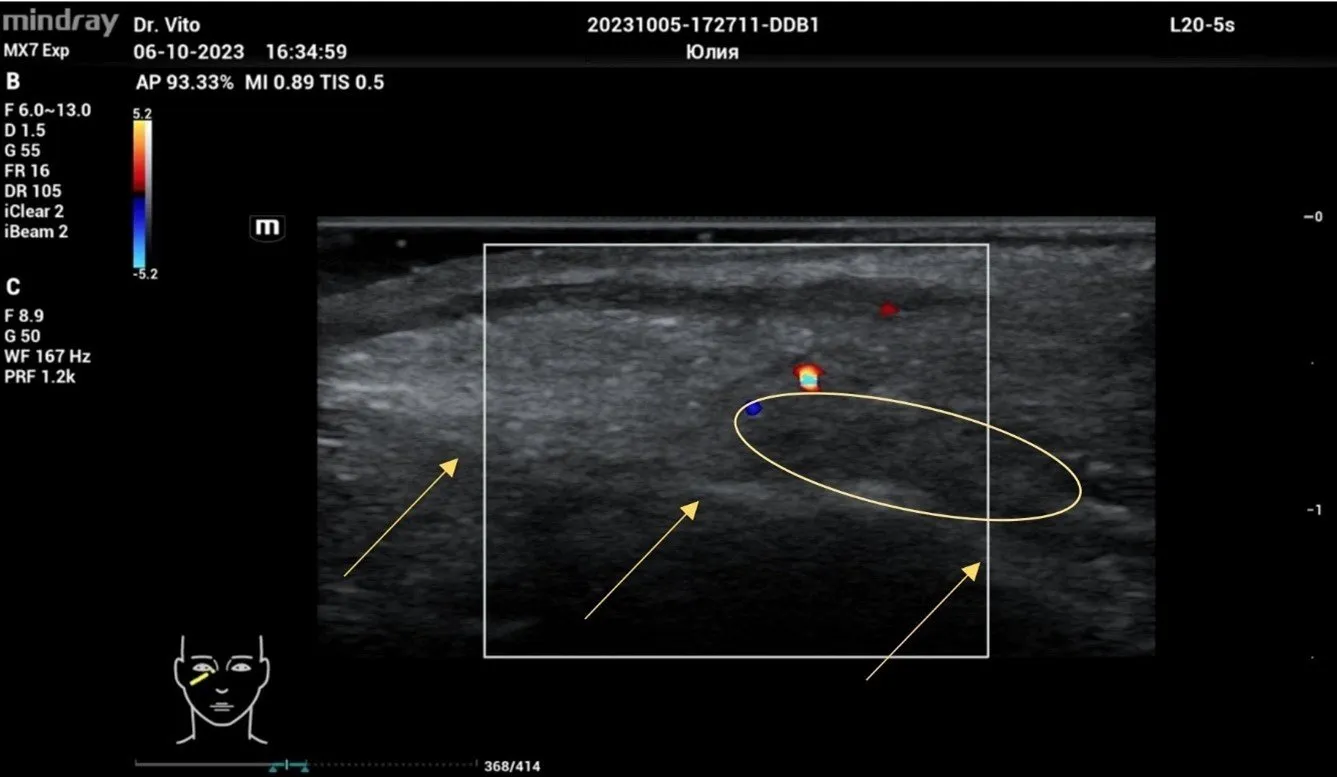

Рисунок 2. Филлер на основе ГК, сразу после процедуры обозначен овалом. Стрелками обозначена надкостница